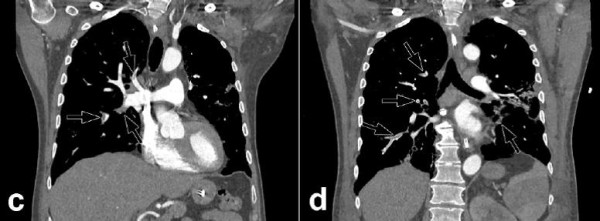

КТА легких 68-летнего мужчины. Исследование проведено через 10 суток с момента возникновения симптомов COVID-19 и в день перевода пациента в отделение интенсивной терапии.

На снимках a и b (аксиальная проекция) стрелками обозначены периферические затемнения по типу матового стекла с участками уплотнения легочной ткани. Объем поражения легочной паренхимы оценивается в пределах 25–50 %. На снимках c и d (фронтальная проекция) определяется билатеральная долевая и сегментарная ТЭЛА.